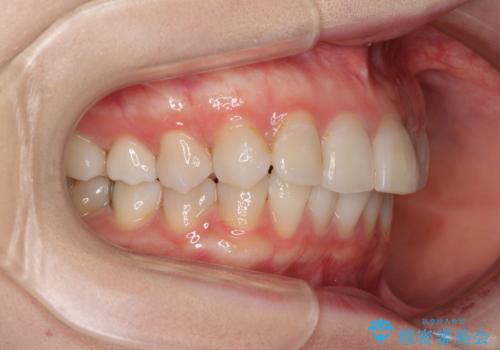

前歯の突出感とデコボコをインビザライン矯正で改善

- 上下前歯の突出感とデコボコを気にして来院された患者様です。

インビザラインによる上下歯列の側方拡大と後方移動、IPR(歯と歯の間を削る)にるスペースの獲得により歯列を整えることとしました。

骨格的な左右差があったため、上下の正中を合わせることができませんでした。

骨格の差は改善できないため、奥歯の咬み合わせに物足りなさを感じましたが、奥歯の咬み合わせによる不自由はなく、口元の突出感も改善することができました。